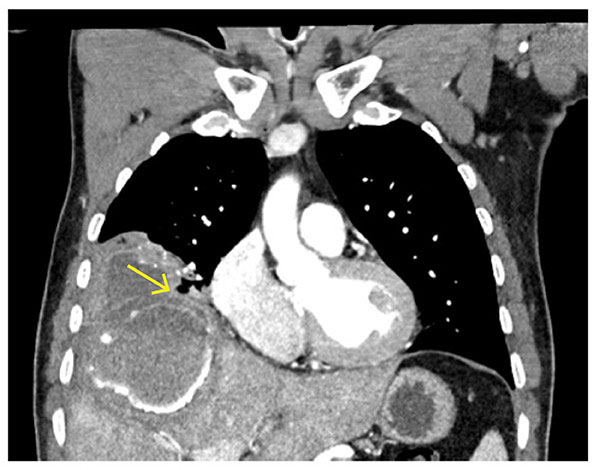

Ved innkomst hadde han lett nedsatt allmenntilstand, blodtrykk på 125/80 mm Hg, puls på 80 slag per minutt, respirasjonsfrekvens på 15 per minutt og temperatur på 38,5 °C. Blodprøver viste hemoglobin 10 g/dL (referanseområde 13,2–16,5), leukocytter 9,7 ∙ 109/L (3,9–9,8), D-dimer 1,39 mg/L (< 0,5), CRP 102 mg/L (< 5), ALP 136 U/L (34–115), nyre- og øvrige leververdier var normale. CT-toraks og -abdomen viste en cyste i segment 8 av høyre leverlapp som målte 6,5 cm x 8 cm i aksialt plan, og 10 cm i kranialt plan. Radiologen var usikker på om det forelå ruptur av cyste ut i bukhulen, eller om cystevæske kun var lekket til et begrenset område subdiafragmalt. Etter mistanke om rumpert ekinokokkcyste, ble det rekvirert ekinokokkserologi, og det ble startet empirisk behandling med albendazol tabletter 400 mg x 2 og prazikvantel tabletter 1800 mg x 2. På dag 7 forelå positive ekinokokkantistoffer, og på dag 14 ble pasienten overflyttet til Rikshospitalet, som har kompetanse på kirurgisk behandling av ekinokokksykdom. De to siste døgnene på lokalsykehuset utviklet han hoste. Ved innleggelse på Rikshospitalet viste ny CT-undersøkelse at levercysten hadde brutt gjennom diafragma og inn i under- og midtlappen av høyre lunge (figur 1). Påfølgende dag ble han operert med torakolaparotomi, en Bloc-reseksjon hvor leversegment 5, 7 og 8, høyre lunges midt- og underlapp og den tilstøtende delen av diafragma ble fjernet i ett sammenhengende preparat (figur 2). Intraoperativt hadde man hypertont saltvann tilgjengelig for å begrense kontaminering ved aksidentell perforasjon av cysten (1). Det tilkom ikke søl av cysteinnhold i buk- eller torakshule. Han ble utskrevet til hjemmet ni dager etter operasjonen, med en etterbehandling bestående av prazikvantel tabletter 1800 mg x 2 i fire uker. I tillegg ble det planlagt minimum seks måneders behandling med albendazol tabletter 400 mg x 2. CT-toraks og -abdomen åtte måneder etter operasjonen viste ikke tegn til restcyster eller tilbakefall.

Som hos vår pasient, kan levercyster gi ubehag i høyre flanke. Cysteruptur kan lede til sekundær ekinokokkose i andre organer. Hos vår pasient brøt cysten gjennom diafragma og infiserte høyre lunge. Frigjort cysteinnhold kan utløse en akutt hypersensitivitetsreaksjon, og i verste fall alvorlig anafylaksi og død (3).